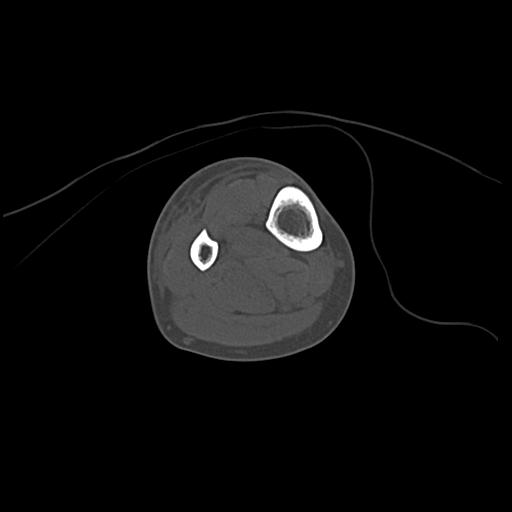

100612 11/25 1/20 右膝 2R 84歳女性 右TKA